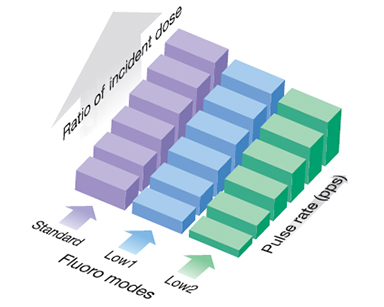

Режимы с изменяемой дозой, включая Grid Pulsed Fluoro

Ultimax-i предлагает 3 режима изменяемой дозы:

- непрерывный

- импульсный

- сеточный импульсный

Пользователи могут выбрать оптимальный режим дозы в зависимости от диагностических потребностей и особенностей пациента.